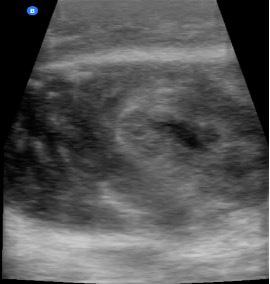

Dr. Artiga’s academic interests include ultrasound, education, and advocacy. Within SAEM RAMS, he has led initiatives such as the Ask-A-Chair educational podcast series, advocacy efforts related to unionization, social media campaigns to promote resident engagement, and the development of board review resources for emergency medicine certification. He has recently taught ultrasound to emergency medicine programs in Latin America.

It was an extremely humbling and eye-opening experience. I went to teach in my father’s country, El Salvador, where I had never visited before. I never truly understood the conditions he lived in beyond his words. All the issues that exist in the U.S. are magnified when you go to countries that don’t have similar resources. Medical decision making is limited by access to resources. It’s not about a lack of capability. I worked with incredibly brilliant doctors who just don’t have access to the same technology or infrastructure we have here. That’s why I believe in supporting ultrasound specifically in these settings. In capable hands, point-ofcare ultrasound can give a clinician life-saving information. Providing this tool and empowering physicians to use it can have a huge impact on individual patients and healthcare systems across the world.

For me, it’s been about chasing my passion and asking, “Who’s on this ride with me?” I’ve always been drawn to ultrasound. Through SAEM’s and the Academy for Emergency Ultrasound’s (AEUS’s) ultrasound didactics and activities, I’ve noticed similar faces showing up. These spaces allow for ideas to connect and develop in ways that don’t happen when you're working alone. You can’t have synergy in isolation. You need people who challenge and inspire you to promote growth. It’s individuals working together, learning from one another, and pushing ideas forward that produce progress.